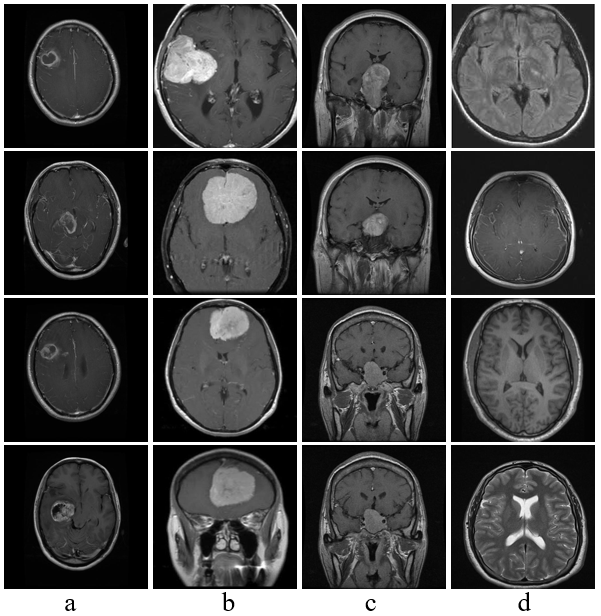

颅内肿瘤是一种严重的神经系统疾病,早期检测对提高患者生存率具有重要意义.然而,现有深度学习模型在颅内肿瘤图像分类任务中仍面临特征提取不足、模型复杂度较高以及类别不均衡等问题.为此,本研究提出了一种轻量化深度学习网络(AD-Net).该网络创新性地引入动态卷积机制,自适应调整滤波器响应,从而增强了对颅内肿瘤复杂、不均特征的表征能力;结合通道注意力机制,有效聚焦关键通道信息,进一步提升了分类的准确性与模型的可解释性.此外,本研究提出了结合二分类与三分类的训练策略,显著缩短了模型训练时间,降低了计算资源的需求,使其更适用于资源受限的医疗环境.在实验中,AD-Net在准确率、精确率、召回率、F1分数以及Kappa一致性系数等关键评价指标上均优于现有主流深度学习模型,验证了其在颅内肿瘤分类任务中的有效性与实际应用价值.

Abstract: Intracranial tumors represent a serious neurological disorder, and early detection is critical for improving patient survival rates. However, current deep learning models for intracranial tumor image classification often suffer from insufficient feature extraction, high model complexity, and class imbalance. To address these challenges, this study proposes a lightweight deep learning architecture, adaptive dynamic network (AD-Net). The network innovatively incorporates a dynamic convolution mechanism that adaptively adjusts filter responses, thereby enhancing the representation of complex and imbalanced tumor features. Additionally, the integration of a channel attention mechanism enables the model to focus on critical channel information, further improving classification accuracy and interpretability. This study also introduces a combined binary and ternary classification training strategy, which significantly reduces training time and computational resource requirements, making the model more suitable for resource-constrained medical settings. Experimental results demonstrate that AD-Net outperforms existing mainstream deep learning models in terms of accuracy, precision, recall, F1 score, and Cohen’s Kappa coefficient, confirming its effectiveness and practical value for intracranial tumor classification.